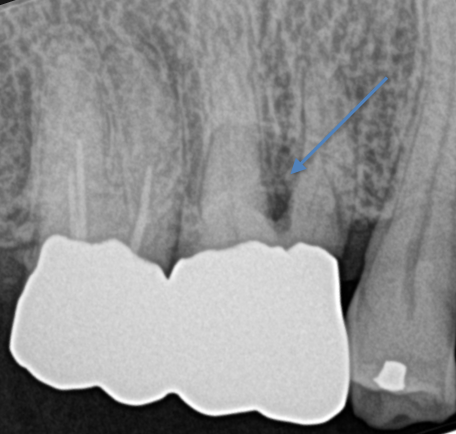

今回のテーマは、奥歯の歯周病で、特に分岐部病変と言われるものでした。

この治療法はドクターによって意見が分かれるところでもあります。

経過観察するにしても、どれくらいの生存率なのか、というところも勉強になりました。